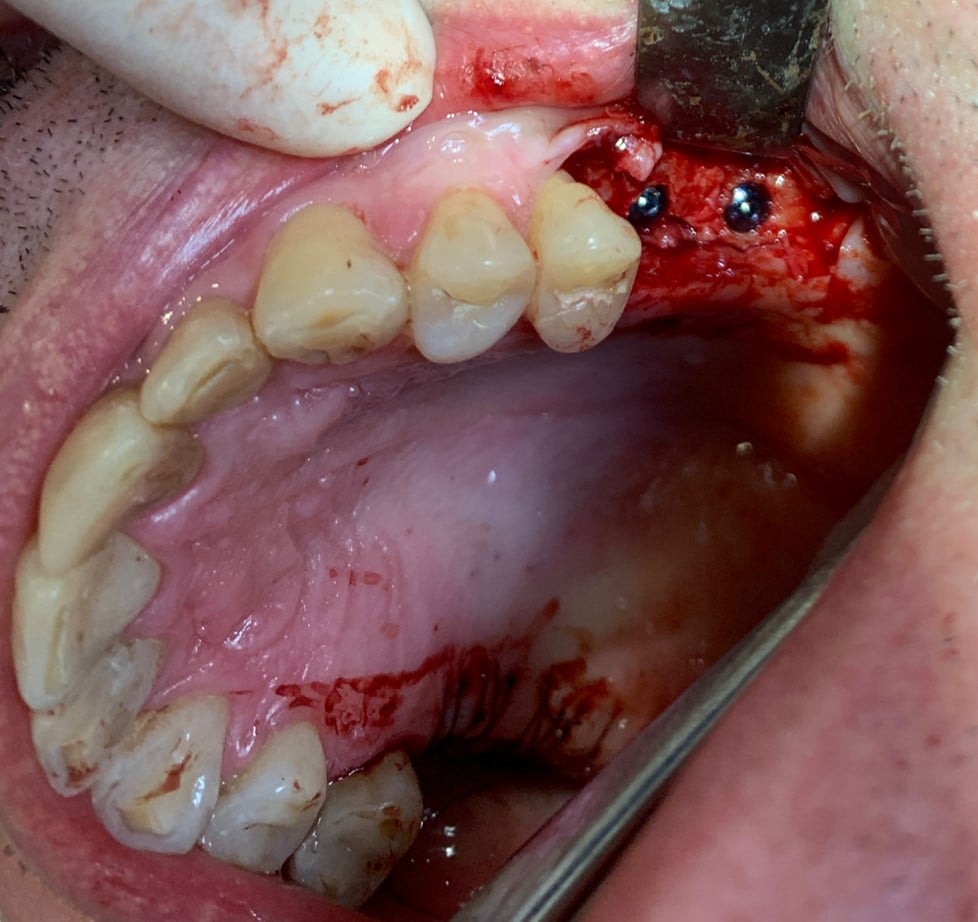

A doua etapă, inserarea implanturilor, a fost realizată după 6 luni.

Împreună cu pacientul, am optat pentru inserarea implantelor cu ajutorul ghidului chirurgical pentru a plasa implantul în poziția protetică ideală și pentru a permite realizarea coroanelor insurubate pe implant. A fost efectuată scanarea digitală a arcadelor și a ocluziei pacientului, iar împreună cu tehnicianul radiolog de la DigiRay a fost suprapus fișierul .stl al amprentei digitale peste fișierul .dcm de la CBCT, utilizând software-ul 3Shape.

S-a planificat individual poziția și axul de inserție al fiecărui implant.